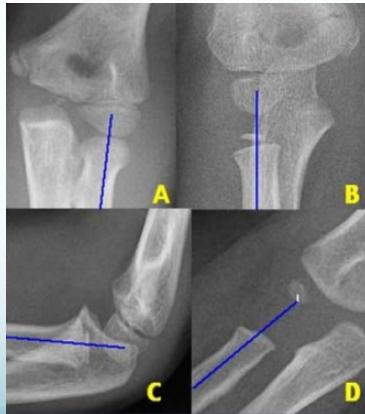

Radio-Capitellar Line:

- A line drawn through the center of the radial neck should pass through the center of the capitellum in all views and in both Extension and Flexion

- If not: dislocated radial head